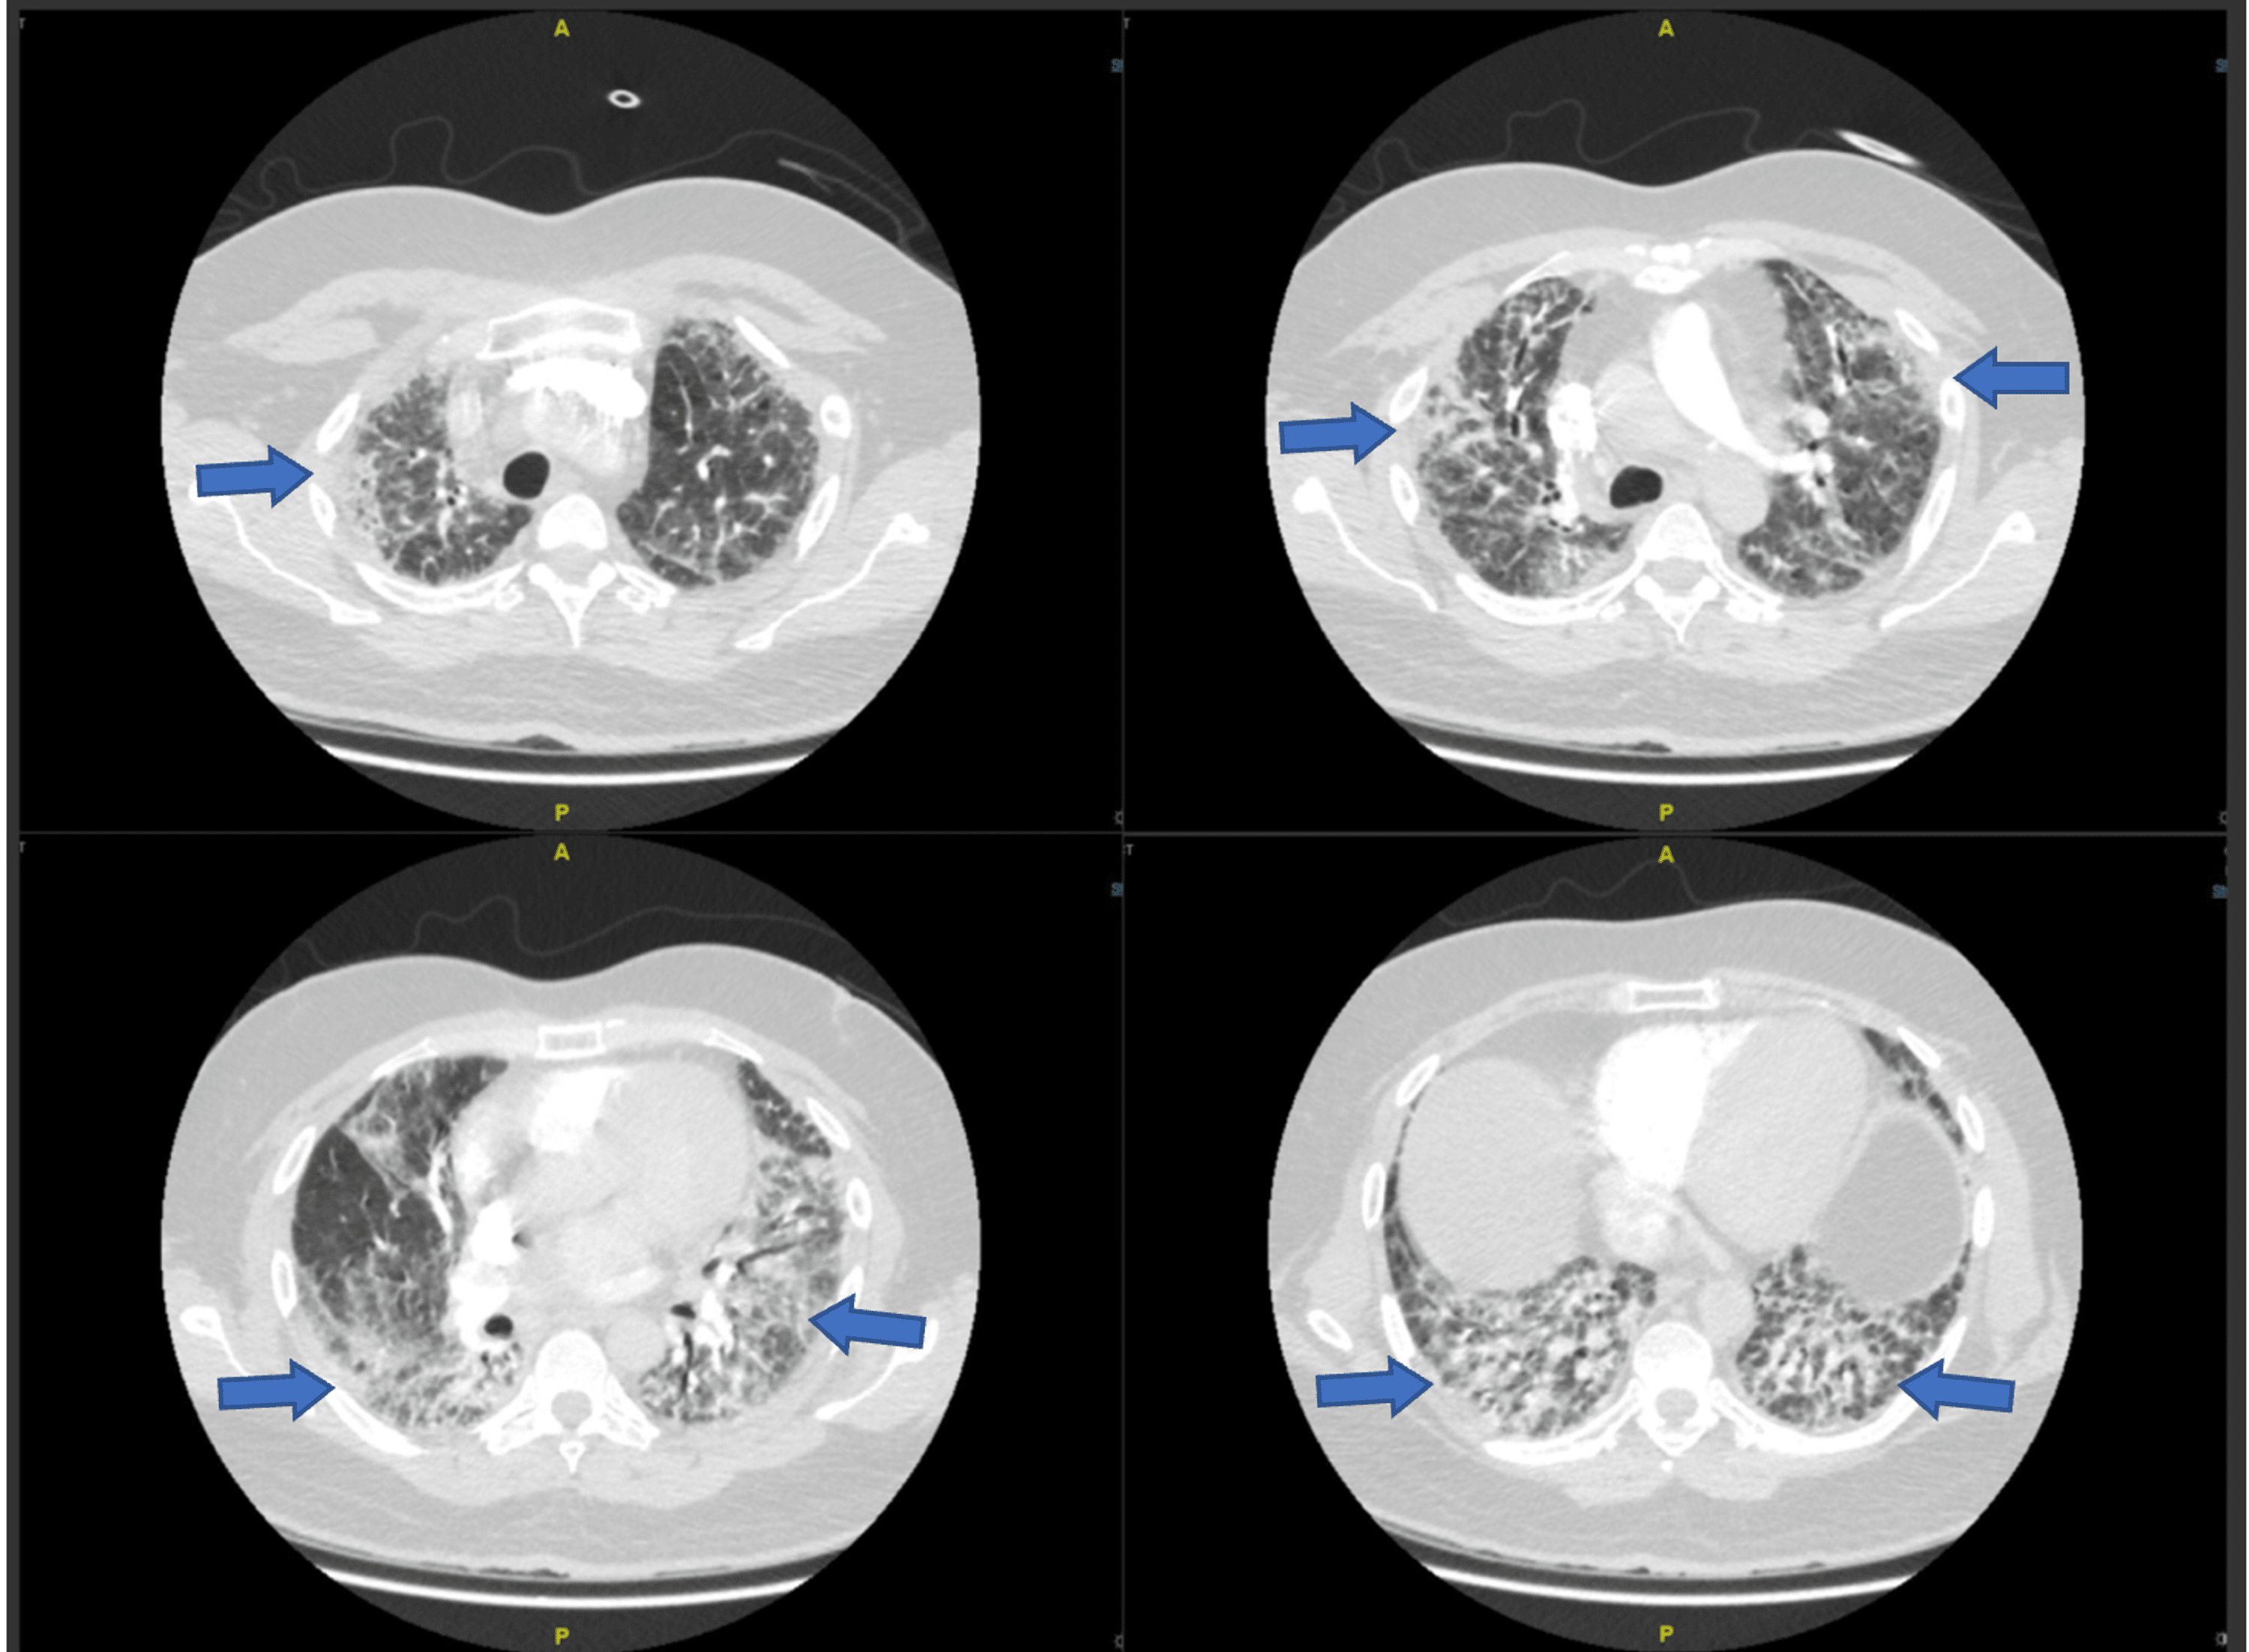

Acute exacerbations of progressivefibrosing interstitial lung diseases Ild Flare Radiology interstitial lung diseases may be marked by abrupt flares of disease activity. interstitial lung abnormalities (ilas) are common incidental findings at ct, which progress over 5 years in more than 50% of individuals, and are. interstitial lung disease (ild) is a category of diffuse parenchymal lung diseases characterized by inflammation. Based on the 2016 definition of. Ild Flare Radiology.